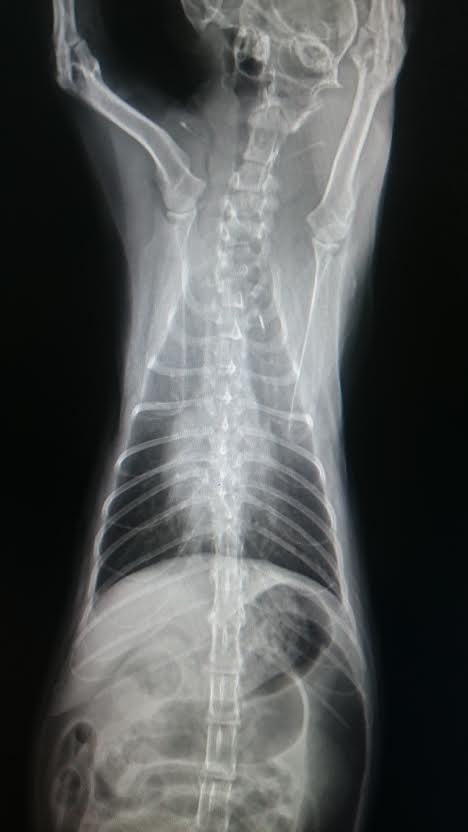

原先因喘息問題住院治療

x光顯示肺部及支氣管有浸潤(發炎)狀況

三日後(3/16)x 光也有逐漸好轉的成像

4/3當日採樣時 小斑又有些許氣喘症狀,x 光顯示肺部跟支氣管有明顯好轉

但是有氣管塌陷的狀況,可能與氣喘有關

住院期間除了做血液檢查及X光外